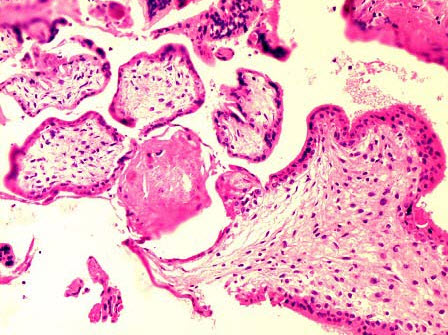

C.血吸虫病

102、单项选择题

患者女性,27岁,不全流产,行清宫术,刮出灰红膜样碎组织共3cm×2cm×2cm。镜检如图,血凝块中大量变性的绒毛,绒毛间质中毛细血管腔内见匀质红染无结构物,这种病变最可能是()

A.微血栓形成